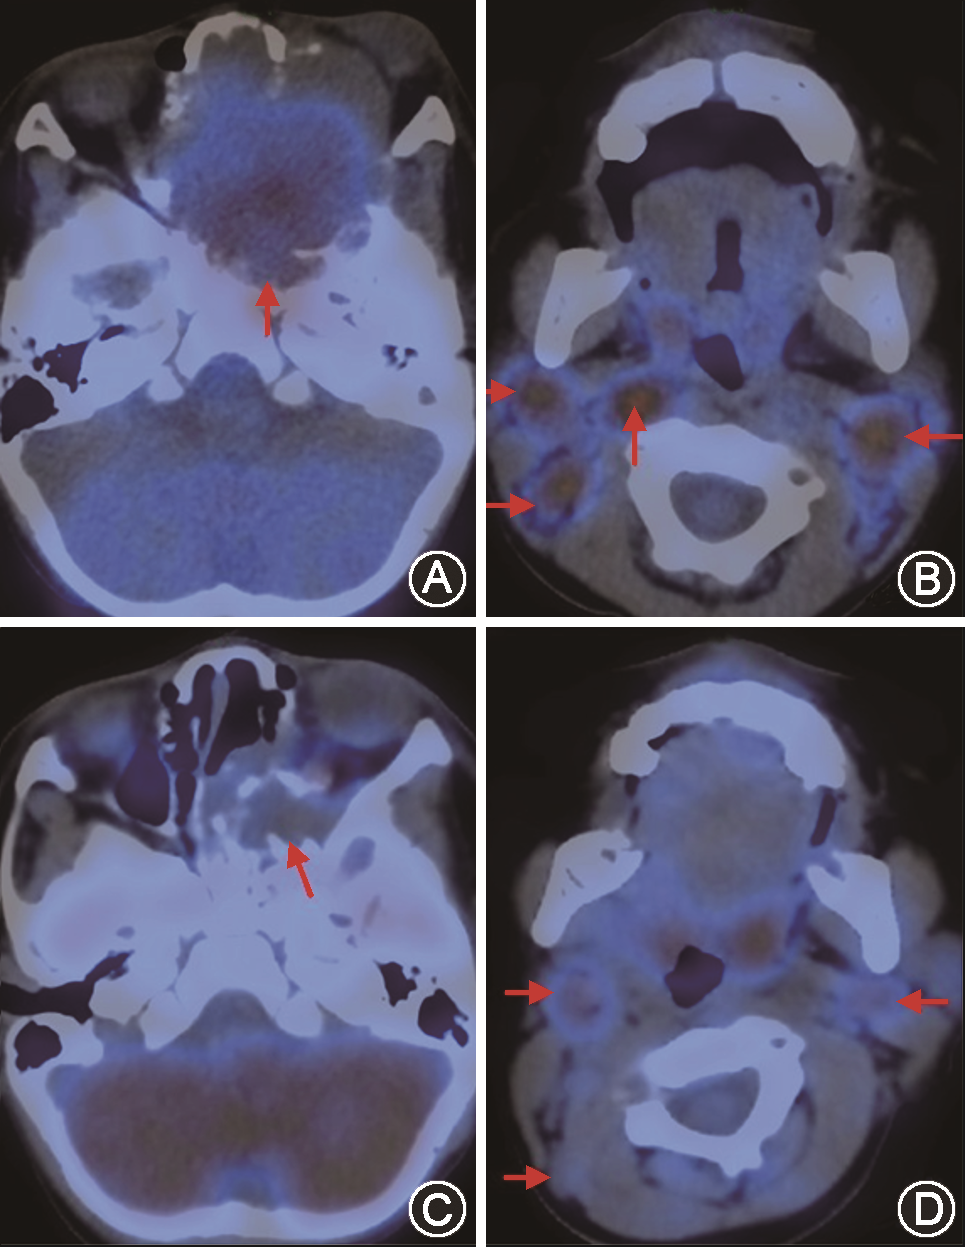

入院后行头颅增强MRI提示:肿物累及双侧鼻腔、鼻窦、前颅底,左侧视神经受压变窄并稍向外移位,左侧海绵窦、前颅窝底硬脑膜受侵(图2A)。PET-CT提示:鼻腔巨大肿块、代谢活跃,肿瘤突入前颅窝底及左侧眼眶,侵犯双侧上颌骨、蝶窦、筛窦、筛骨及蝶骨、左侧颞骨(图3A),双侧咽旁间隙及双侧颈Ⅱ区、左颈Ⅰ区多发代谢活跃淋巴结,考虑转移瘤可能性大(图3B)。左眼内直肌、下直肌、视神经受压;余全身未见转移征象。血红蛋白浓度81.00 g/L,甲胎蛋白(AFP)43 230.5 ng/ml。中山大学附属第三医院病理科会诊外院病理切片,加做免疫组化后提示:核分裂相易见,瘤细胞排列呈网状、管囊状、乳头状及小管状,可见嗜酸性玻璃样小体,结合免疫组化结果,符合卵黄囊瘤(图4A)。

患儿入院后经病理科、影像科、核医学科、儿科、神经外科多学科会诊后认为:目前肿瘤巨大,突入前颅窝底及左侧眼眶,且视神经受压。属于卵黄囊瘤Ⅳ期,并且中枢神经系统侵犯,肿瘤完整切除难度较大,手术治疗极易出现颅脑及眶内并发症,大大降低患儿生存质量。可先行术前化疗,待肿瘤范围缩小后,争取手术时机。遂转入儿科行PEB方案(顺铂、依托泊苷、博来霉素)先后进行6个疗程化疗,第3个疗程结束后患儿AFP降至正常水平。3个疗程后患儿左眼球前突明显好转(图1B),头颅增强磁共振扫描显示肿瘤较前明显缩小(图2B)。PET-CT提示:原鼻腔肿物较前明显缩小,大部分区域代谢恢复正常(图3C)。双侧颈Ⅱ区、左颈Ⅰ区淋巴结代谢较前降低,部分恢复正常(图3D)。遂转入我科全麻下采用神经手术导航系统经鼻内镜下左侧颅底肿瘤切除、鼻窦开放术,术中见瘤体主要位于翼腭窝,上至眶底、眶内侧及前颅底,下至总鼻道,内至鼻中隔、蝶窦腔,外至翼腭窝、颞下窝,经翼内肌、翼外肌内侧至蝶窦及斜坡前方。病变区域为大量机化组织及粗糙骨小梁样物,切除前颅底病变并磨除部分骨质直至显露正常骨质,沿眶筋膜层面将肿瘤组织连同眶纸板一并切除。经后囟进入翼腭窝,经导航定位肿瘤外侧界后,将瘤体整体分离,见边界尚清,未损及颌内动脉。至此,瘤体完整切除,标本送病理检查。术中出血约200 ml,输血RBC 1 U。